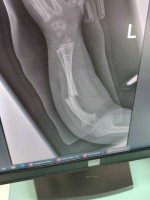

Madzia choruje na wrodzoną łamliwość kości typu III (osteogenesis imperfecta) – rzadką, genetyczną chorobę tkanki łącznej, która powoduje skrajną kruchość kości. Złamań doznała już w życiu płodowym, a jej organizm nie produkuje kolagenu. Choroba jest nieuleczalna, a leczenie ma charakter objawowy i obejmuje stałą rehabilitację, liczne operacje, stabilizację kości oraz specjalistyczną farmakoterapię. Dziewczynka ma za sobą już kilka poważnych zabiegów oraz kilkanaście podań leków wzmacniających kości. Przed nią kolejne operacje i intensywna fizjoterapia, bez której trudno byłoby myśleć o większej samodzielności.

Foto: Licytacje dla Madzi Sulki.